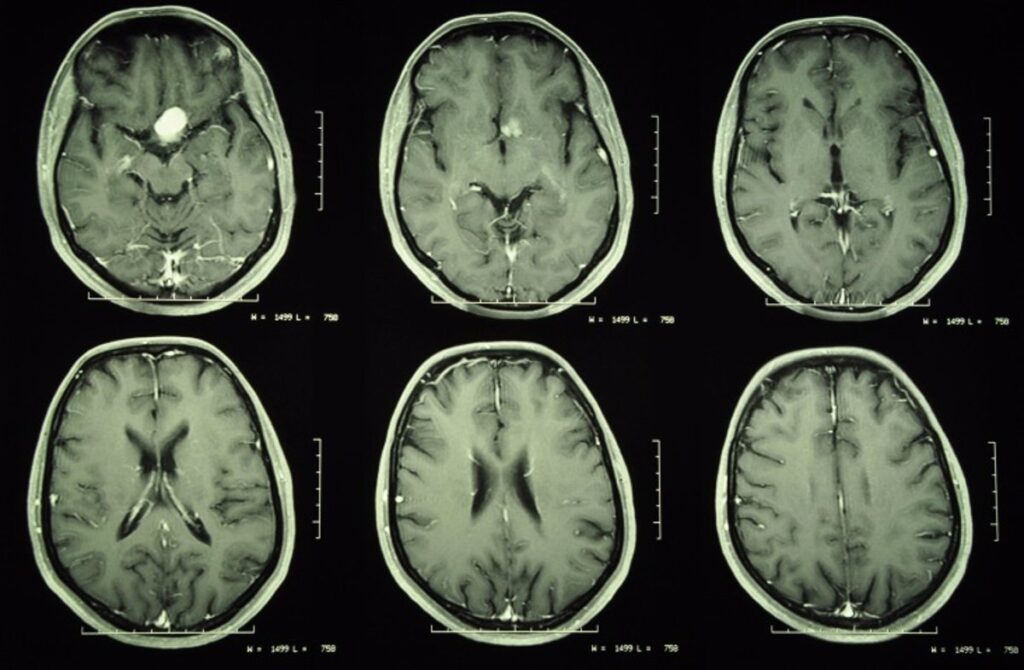

Los meningiomas son tumores que crecen en el tejido conectivo que rodea el cerebro y la médula espinal. Son el tipo más común de tumor cerebral primario y, si bien no suelen propagarse a otras partes del cuerpo, pueden crecer sin control y provocar una compresión incapacitante y mortal de los nervios y el cerebro.

El tratamiento estándar para los pacientes con meningiomas es la extirpación quirúrgica o la radioterapia externa cuando los tumores crecen en zonas donde la cirugía es demasiado peligrosa, como cerca del tronco encefálico o la médula espinal. Pero en la parte de los pacientes en la que el tumor crece a pesar de estos tratamientos, conocida como meningioma refractario, los tumores tienden a comportarse de manera más agresiva y es difícil volver a tratarlos porque la radiación y la cirugía no se pueden repetir con frecuencia sin mayores riesgos.